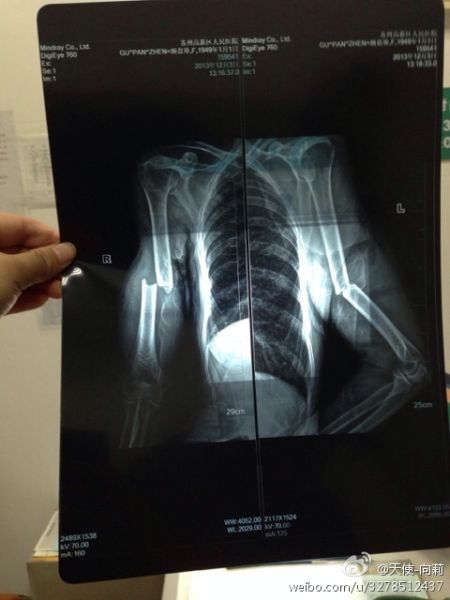

圖為微博上傳的“范木根的妻子顧盤珍手被打斷”

圖為微博上傳“范某某的妻子顧盤珍手被打斷?!?/font>